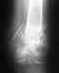

Но в апреле 2012 года у меня была серьезная травма - упала в ванной на локоть. В результате травмировался локтевой нерв и по типу противоудара травмировалось плечо (повредилась связка). Поносила на косынке. Потом была операция на колене и пришлось прыгать на костылях. Ситуация усугубилась появилась боль. Пошла на консультацию к врачу. Сказал носить ортез по типу Дезо 2 месяца. А на следующий день упала на асфальт и опять же травма пришлась на локоть и колени. Боли были сильные, сделали рентген, переломов не обнаружили и я перестала носить ортез. В связи с этим пошли вывихи ночные. за месяц их было порядка 8 штук. Опять одела ортез. На консультации с главным ортопедом нашего города была предложена операция по Латерже, так как кроме разрыва суставной губы, есть вколоченный перелом головки плеча и клювовидного отростка. Но эффективность дает всего 60%. Для меня это мало. На данный момент с сентября 2012 уже было порядка 12 вывихов и 4 подвывиха, и не только ночных. С каждым разом боль сильнее и труднее вправить руку. Головка плеча постоянно болит. Вопрос: обязательно ли надо делать операцию. Можно ли без нее обойтись, не принеся себе вреда? И есть ли более эффективная операция, чем костная пластика по Латерже? Ведь если я правильно понимаю, что если операция будет неудачной, то следующая стадия - это эндопротизирование? Заранее благодарна.